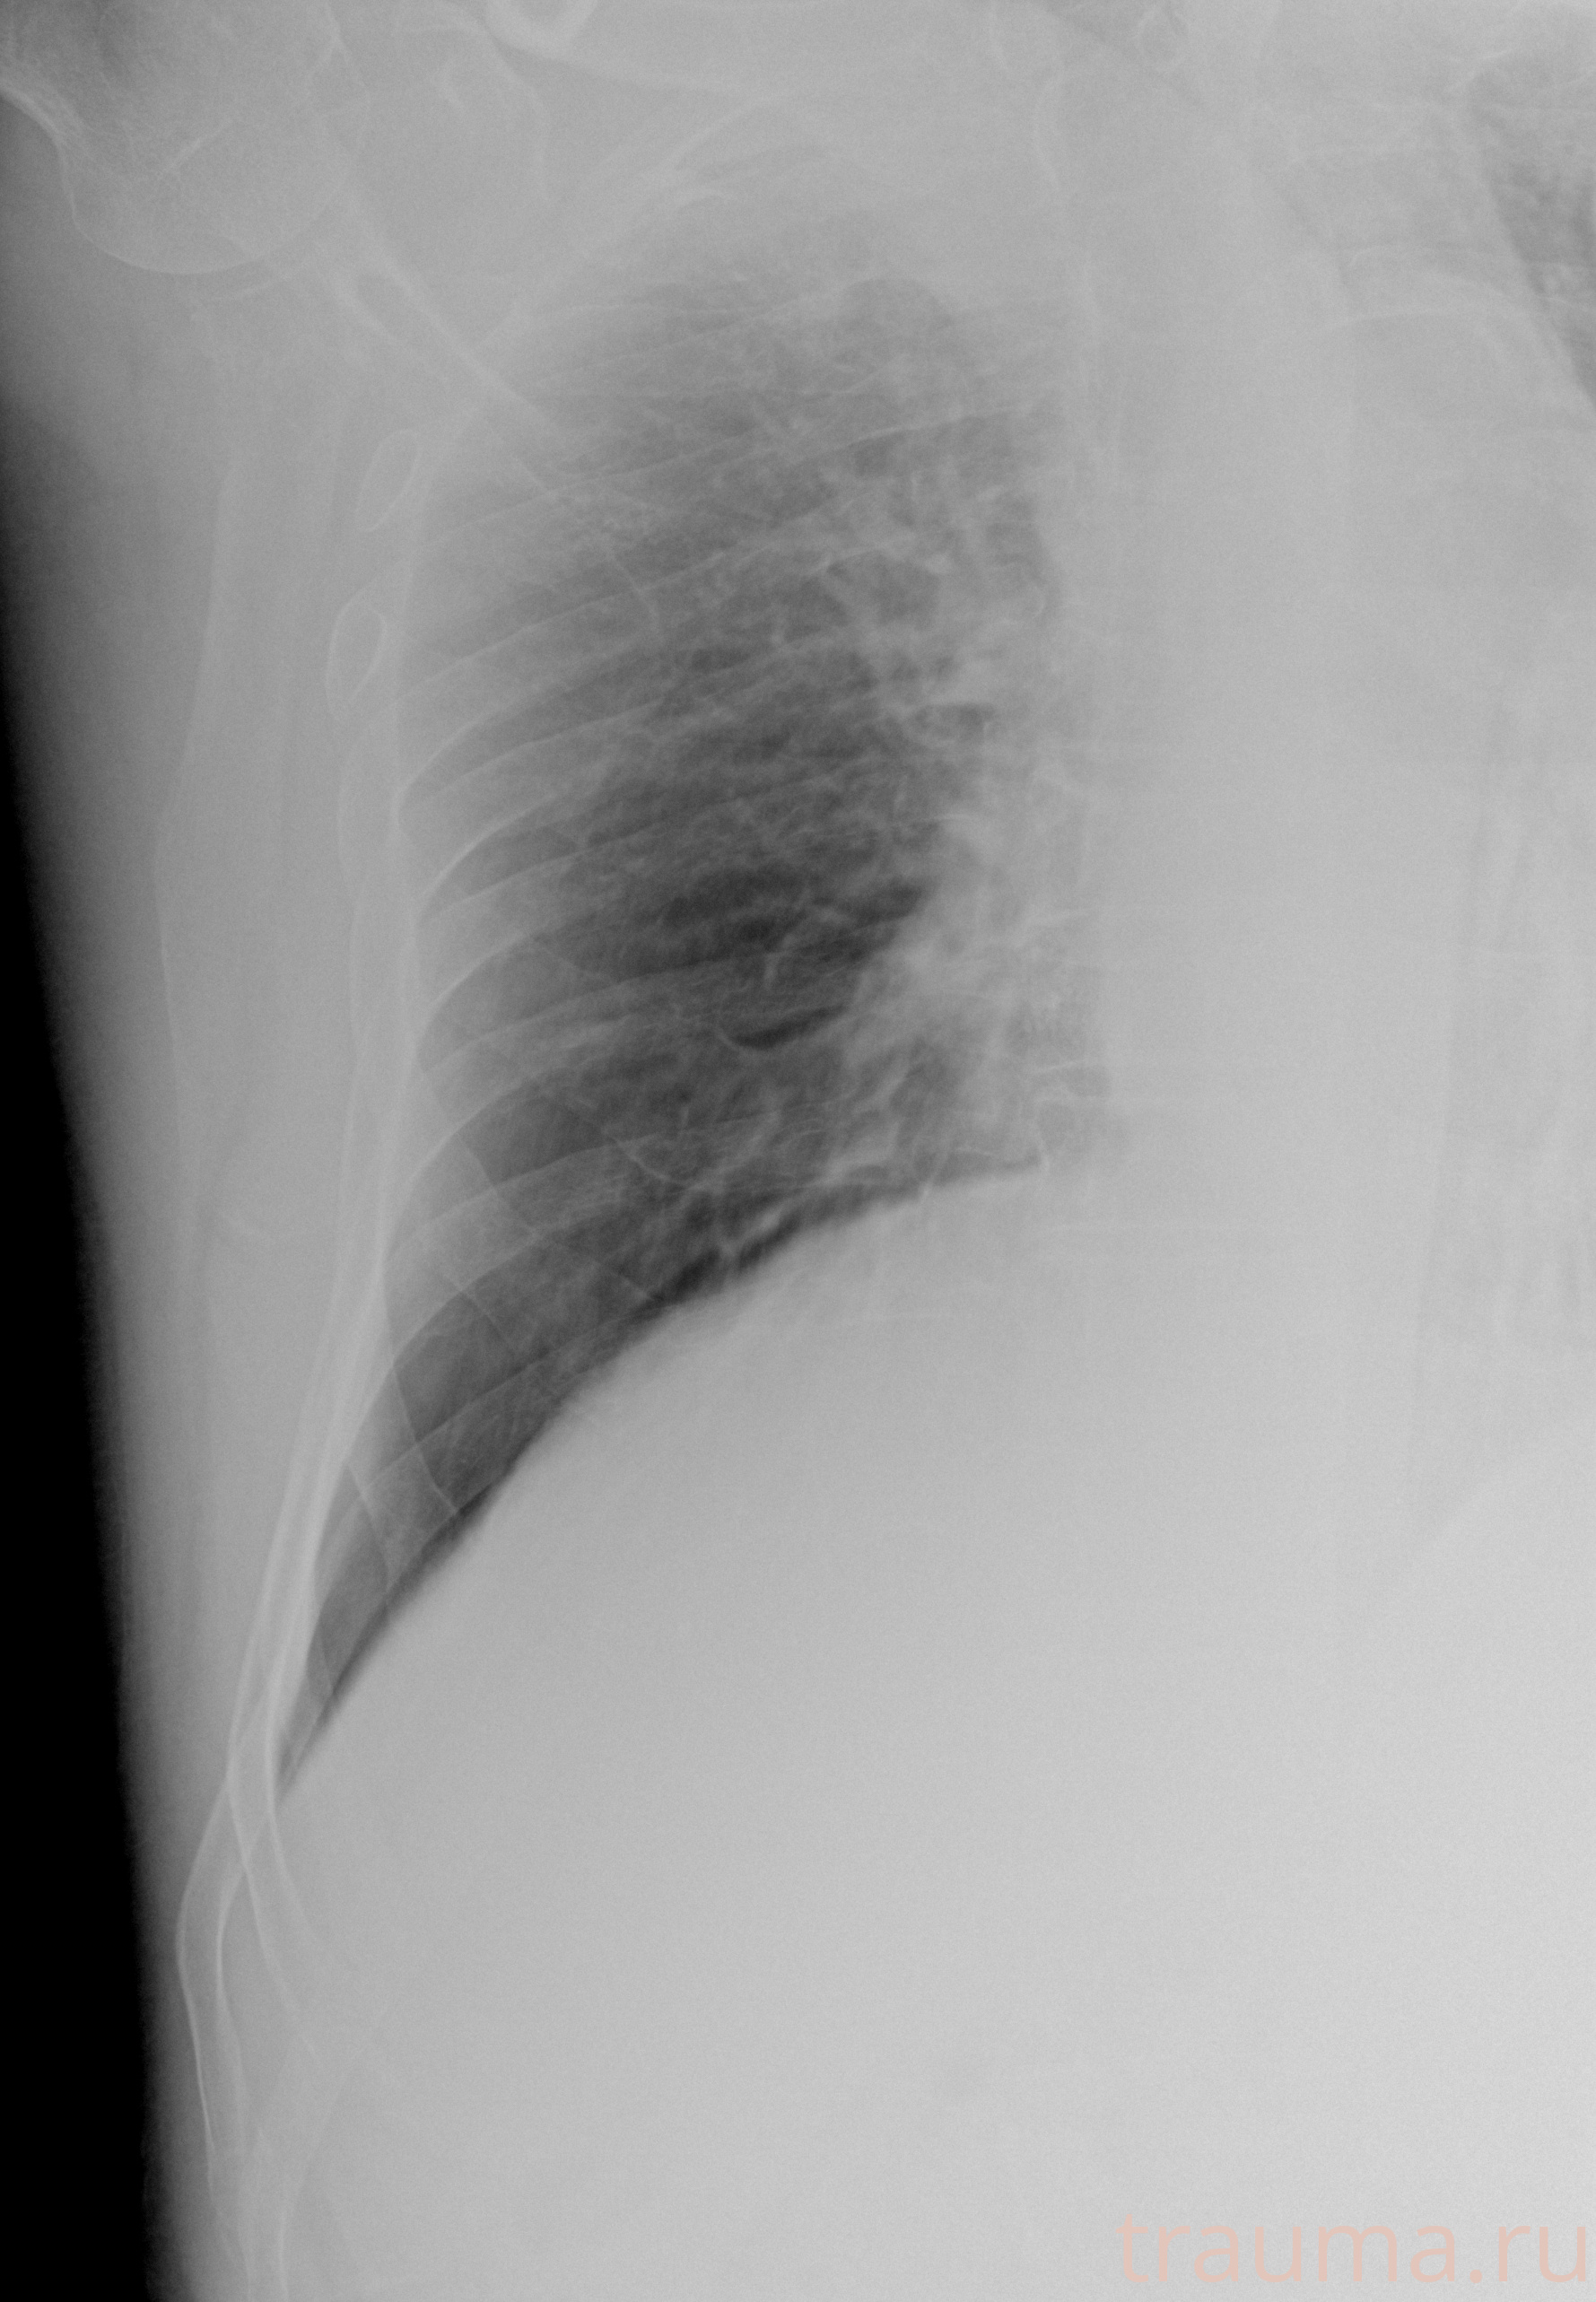

Рентгенограммы

Рентген на дому: по вашему адресу приезжает врач-рентгенолог, травматолог-ортопед с мобильным рентгеновским аппаратом, проводит диагностику травмы или заболевания, делает необходимые рентгенограммы, дает рекомендации по дальнейшему лечению. Получить качественные снимки в домашних условиях возможно благодаря уникальной методике, разработанной МосРентген Центром для института  Склифосовского

при переломе шейки бедра и пневмонии от компании МосРентген Центр - партнера Института имени Склифосовского